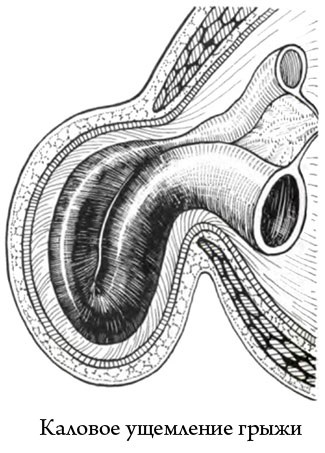

2. încălcarea fecale

ciupirea Fecal apare bucla intestinală overflow în interiorul sacului herniar. În acest caz, circulația sângelui în intestin bucle în interiorul sacului herniar.

Atunci când încălcarea fecale de efort fizic și sarcina pacientului este mult mai puțin semnificativă decât în elastic. Importanța principală este o încălcare a funcției motorii a intestinului si adeziunile în cavitatea abdominală *.

* Spikes - o fuziune de tesut care conecta lung spatiul procesului inflamator.

Acest tip de patologie este tipic pentru persoanele în vârstă.